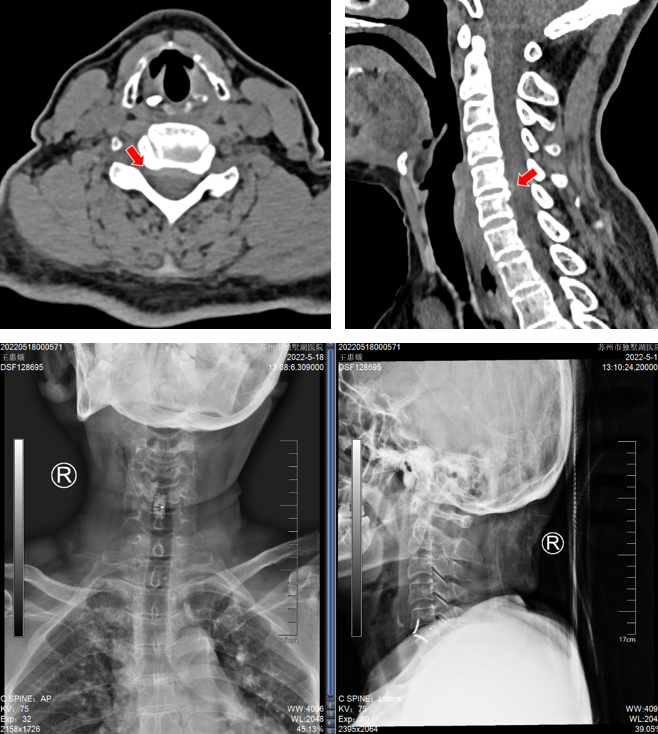

沈阿姨今年58岁,原本正是准备享受生活的年纪,但在今年5月,困扰了她长达4年的颈肩痛明显加重了。短短一周时间,沈阿姨的右上肢就出现了麻木感,吃药、理疗完全无法缓解,症状发展很快,于是立刻来我院骨科就诊。颈椎CT上可以清晰看到,她C4-5的椎间盘明显向右后方突出,椎间隙后缘骨赘增生,导致神经根受压。

(颈椎CT提示患者C5-6的椎间盘突出棒骨性狭窄)

(颈椎CT提示患者C4-5的椎间盘突出(右后方),椎间隙后缘骨赘增生)